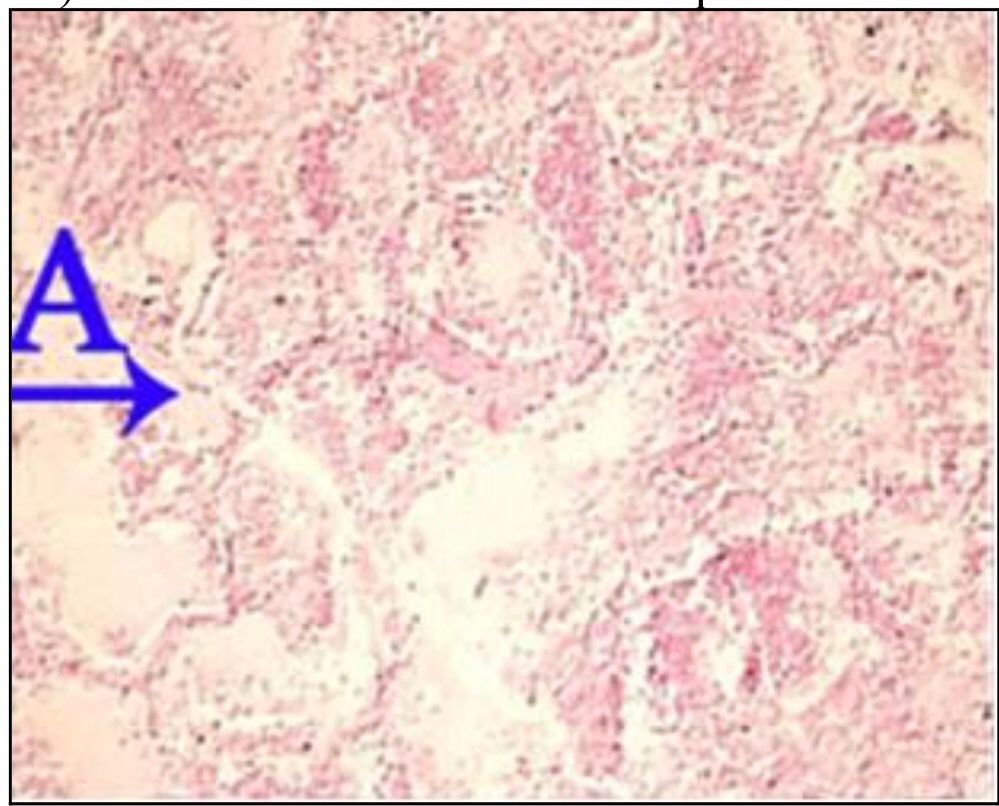

Question 72

Question

What is the correct answer at point A?

Answer

• - lésion segmentaire hétérogène

• - lésion de la muqueuse bronchique

• - lésion alvéolites suppurée

• - épithélium respiratoire

• - lumière comblée de nécrose suppurée

Question 73

What is the correct answer at point B?